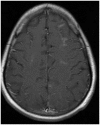

Results: Eight out of the 20 patients included in the study were on cyclosporine or tacrolimus based immunosuppressant therapy for kidney transplant. Four patients had severe hypertension at presentation. The most common MRI finding was high T2-fluid-attenuated inversion recovery (FLAIR) signal in the cortex and subcortical white matter of both cerebral hemispheres, particularly in the parietal and occipital lobes (n=16). The second most common MRI finding was increased leptomeningeal FLAIR signal (n=7). Out of seven patients with leptomeningeal signal, five demonstrated leptomeningeal enhancement as well. Four out of these seven patients had no other parenchymal findings.